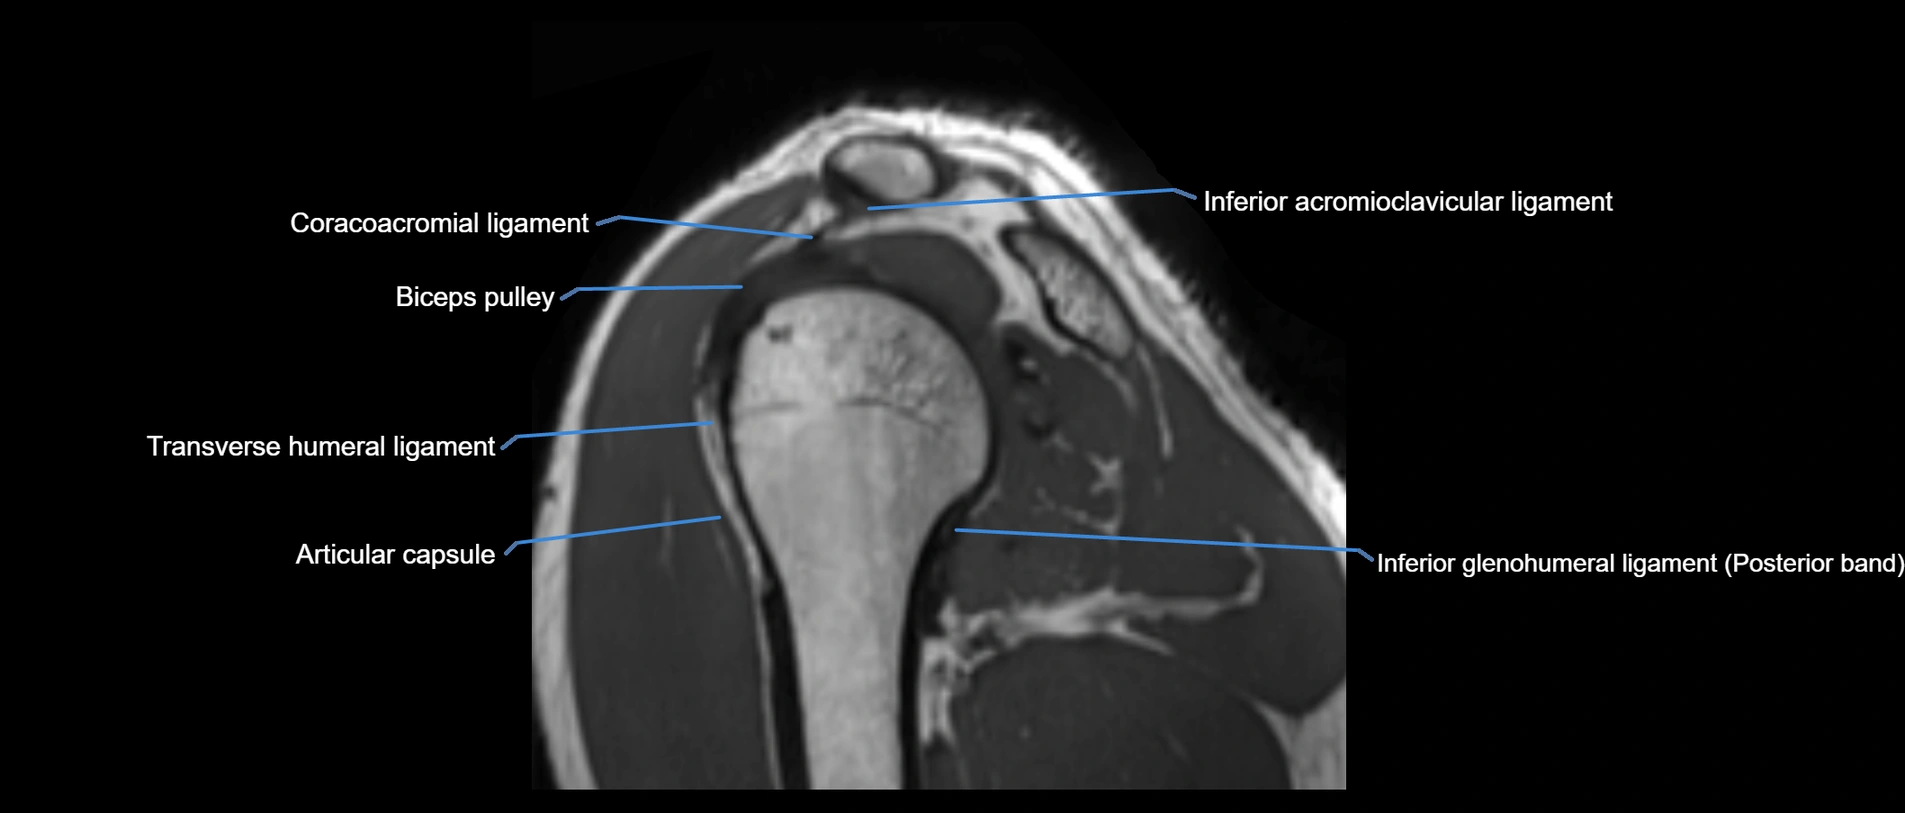

MRI images

image